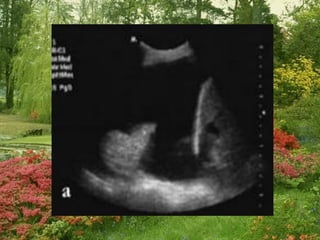

Tissue pattern representative of Alveolar

Consolidation

Presence of hyperechoic punctiform

imagesrepresentative of air bronchograms

Pleural

effusion

Lower lobe

Tissue pattern representativeof Alveolar Consolidation Presence of hyperechoic punctiform imagesrepresentative of air bronchograms Pleural effusion Lower lobe